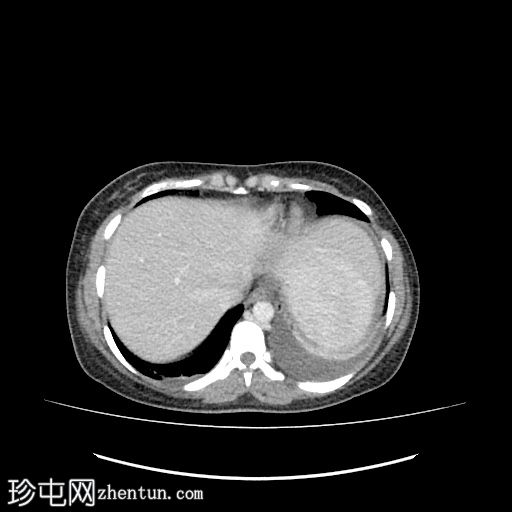

轴位增强扫描

门静脉期

肝下区可见一大小约15 x 15.2 x 8.6 cm的较大、边界清晰、呈不均匀强化的实性肿块。

该病灶压迫胃小弯、幽门和胃窦,并对肝脏产生占位效应。门静脉和下腔静脉受压,但脂肪间隙保持完整,未见明确的血管侵犯。

肿块左侧可见正常的胰尾。胰管未见扩张。

肝内胆管和胆总管管径正常。